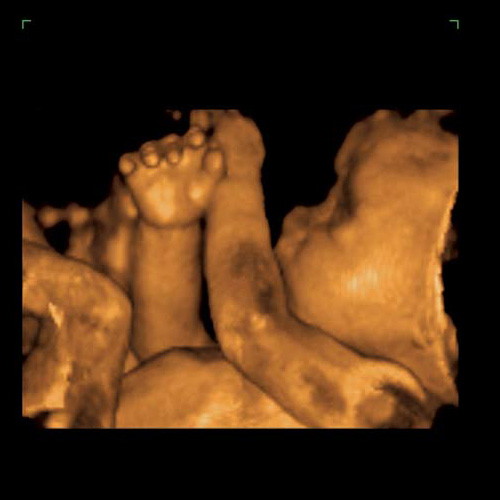

ecografía. ¿Qué se ve? ¿eh?

¿Un ser humano de la especie hombre?

-¿Cree que si más madres pudieran ver a sus bebés en una ecografía elegirían no abortar?-Sí. Una de las preguntas más frecuentes que me hacían las mujeres durante las asesorías era: “¿Mi bebé sentirá algo durante el aborto?” En Planned Parenthood me enseñaron que “no, que el bebé no siente nada”. Ellas preguntan porque les importa su bebé y quieren asegurarse de que este “procedimiento médico” no le hará daño a la vida que crece dentro de ellas. Sé que si esas mujeres hubieran sabido que su bebé sentiría el aborto, que sufriría dolor y que se sentiría atacado, muchas no habrían abortado.